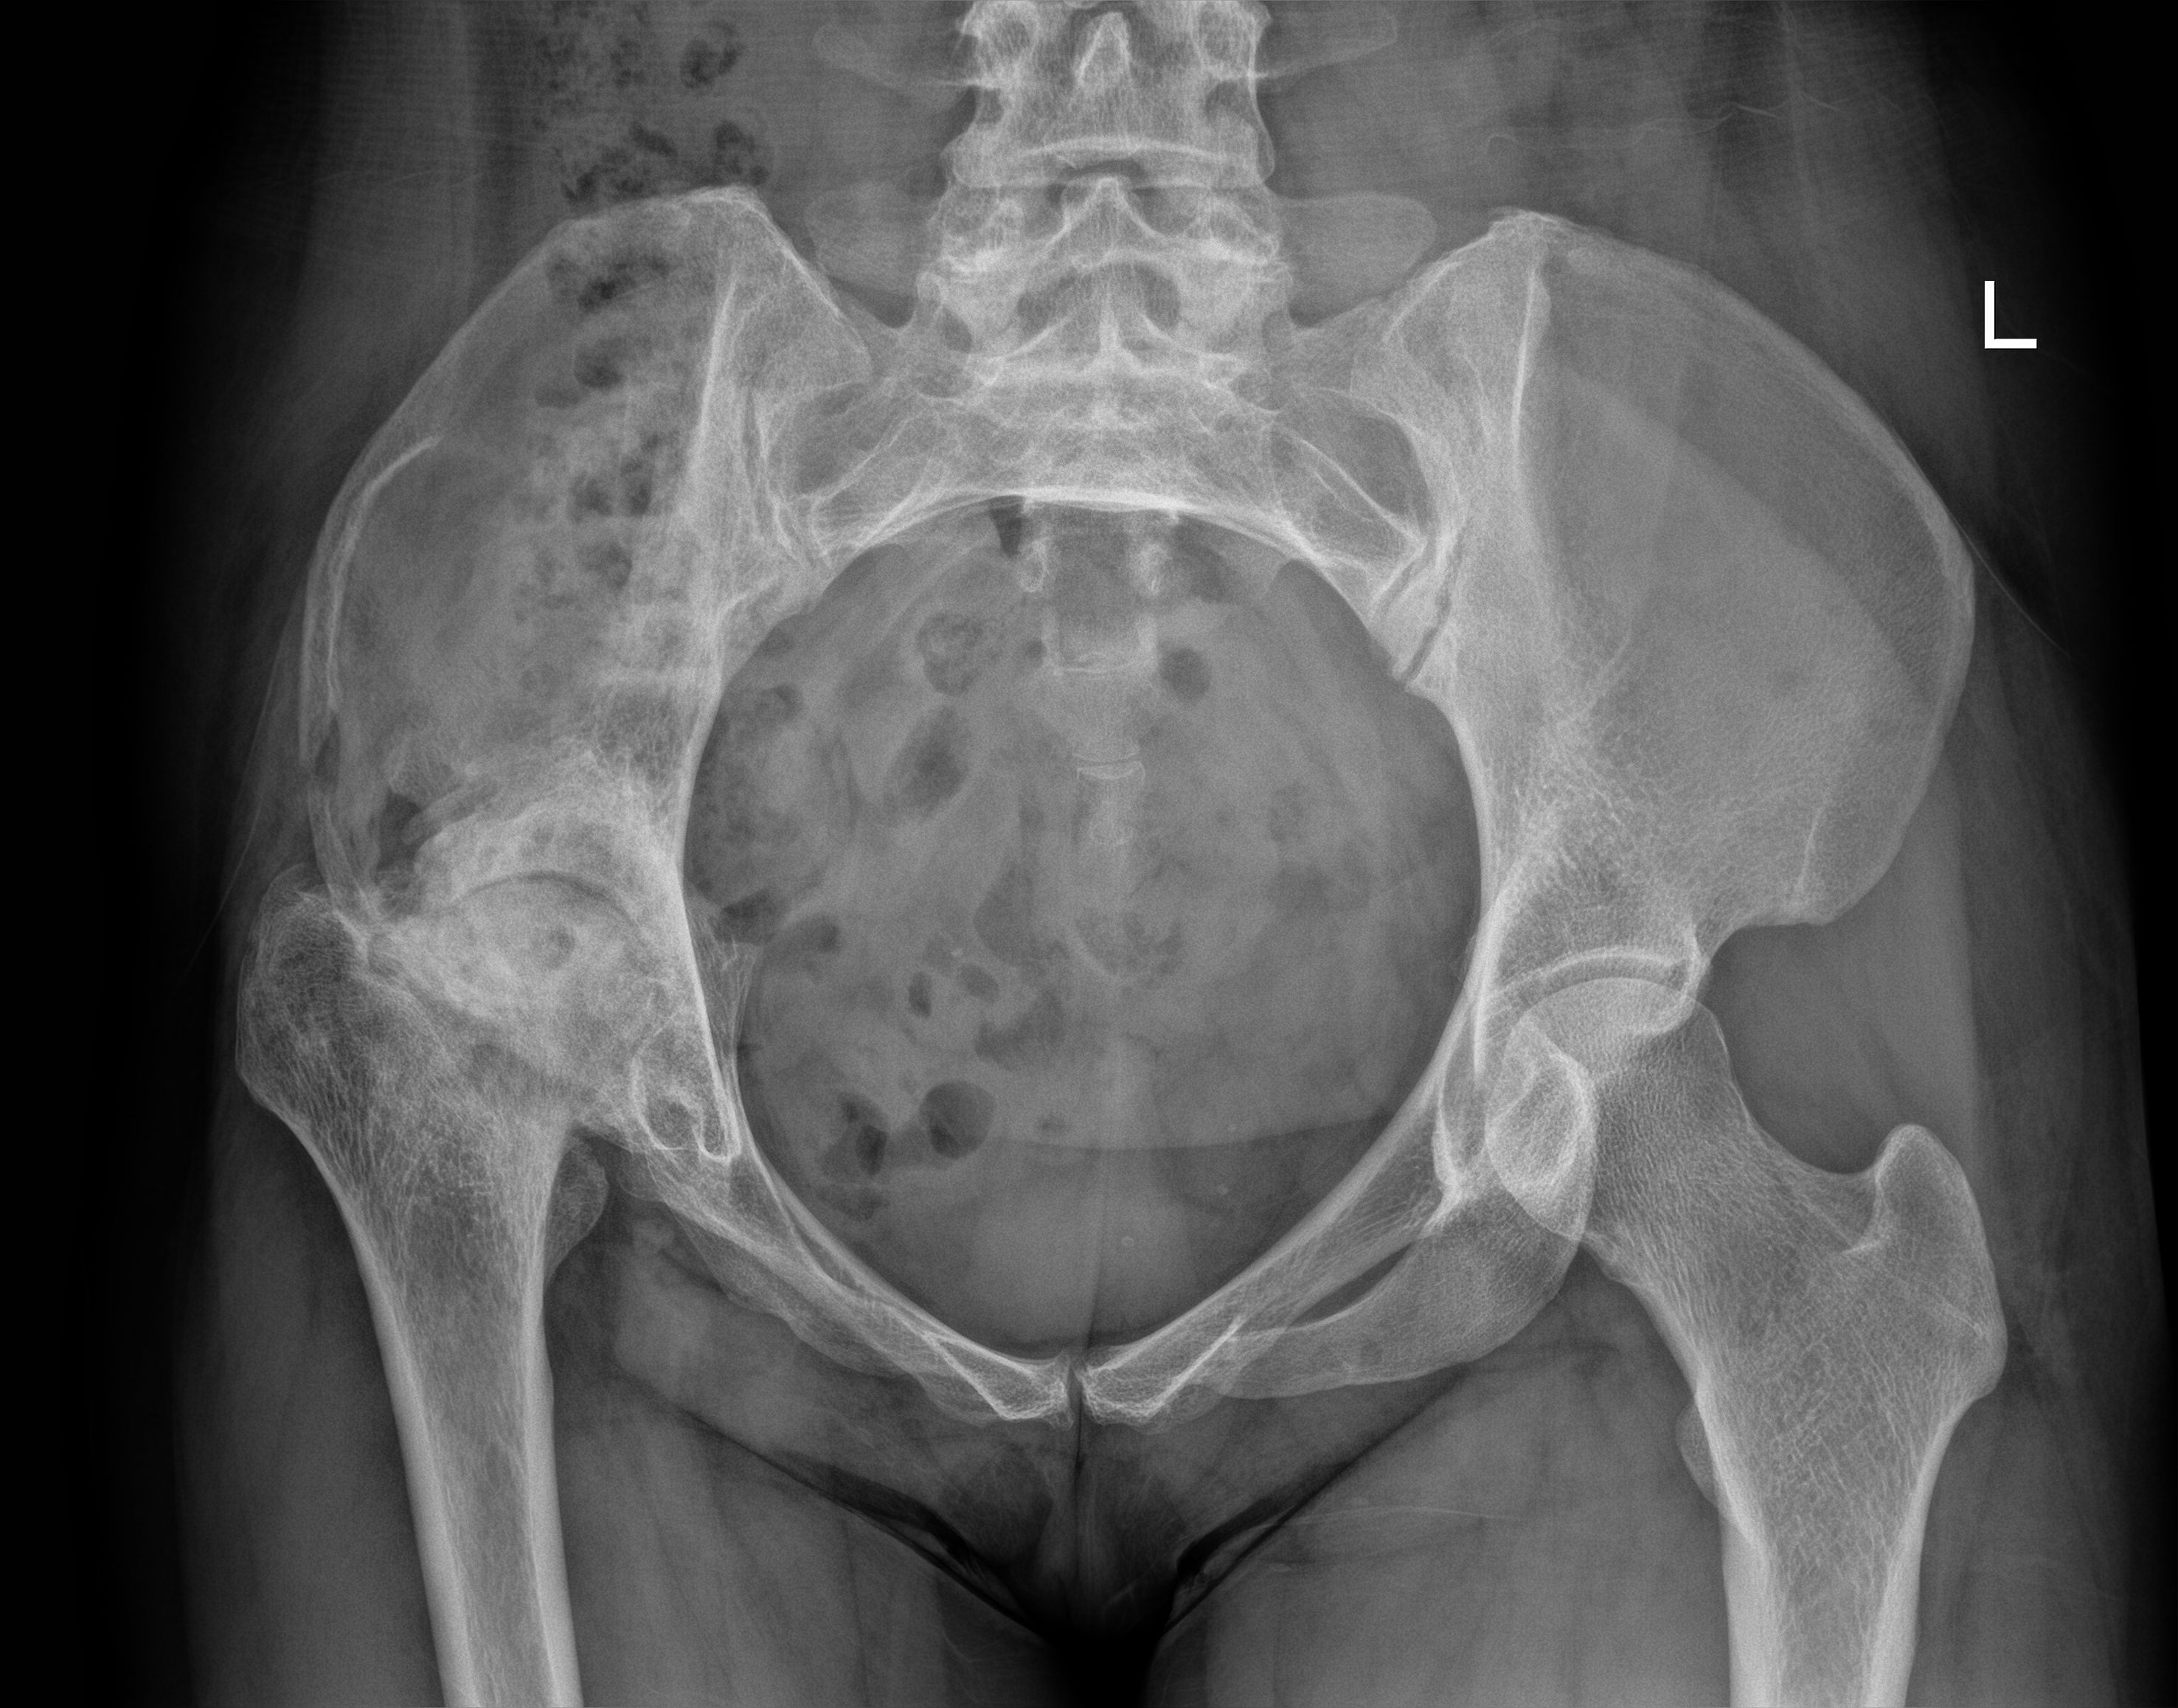

Figure 5

Figure 5. An anteroposterior pelvic radiograph on postoperative day 3 demonstrated no aberrant signal in the right ilium, with partial visualization of the bone graft shadow.